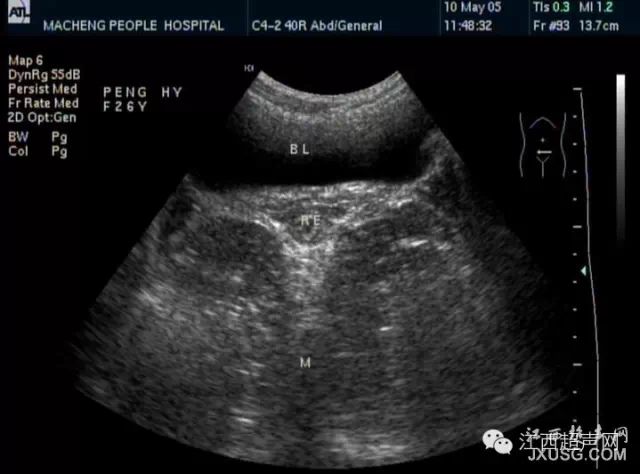

5.遇到过一个女性患者,20多岁。停经2个月,流血待查。尿憋的相当的多,膀胱压迫致使宫腔下段显示不清,上段典型葡萄胎表现。排尿后再查,于宫腔下段探及不均质强回声。为不全流产表现。